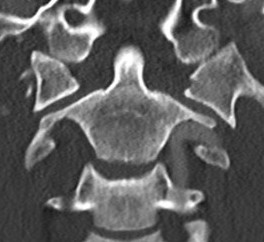

Landell's Classification

Type 1.  Isolated lateral mass fracture

- axial compression and lateral flexion

C1 lateral mass fractureAtlas lateral mass